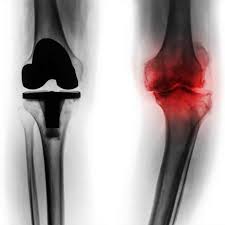

Knee replacement is a common procedure most often used to treat pain and disability caused by osteoarthritis.

Signs of knee replacement failure. These include but are not limited to the following. Here are a few of the postoperative symptoms to look for that could indicate that your new depuy knee replacement device is failing. Stiffness when signs of stiffness become evident the patient immediately losses range of motion.

Symptoms of a failed knee replacement there are a number of warning signs any person who has undergone knee replacement surgery should be aware of including a large amount of soreness or swelling in the affected joint. The first symptom is pain. Knee replacement is a surgical procedure in which the damaged or disease knee joint is replaced with an artificial prosthetic implant. Replaced knees can exhibit warmth in the joint for months after surgery but this effect steadily decreases over time.

The other signs that will creep up as a result of stiffness include pain and functional deficit. Knee replacement is one of the most common joint replacement procedures worldwide followed by hip replacement surgery. There are a few key signs of knee replacement failure. Deep infection is a rare but serious complication that occurs in about 1 of knee.

Symptoms may include pain swelling stiffness and lack of stability. In addition to the swelling that can occur another symptom of a failing prosthesis can include noticeable warmth of the joint. There are few things that can increase the chances of successful knee replacement. Pain is never good and the purpose of getting a new knee in the first place is to relieve knee pain so that you can get back to work or back to enjoying a normal retirement.